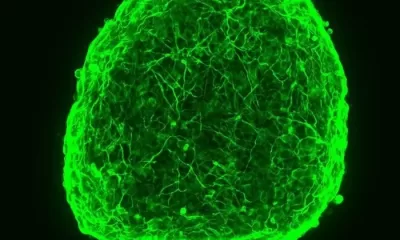

Studies of a ‘future-proof’ vaccine candidate have shown that just one antigen can be modified to provide a broadly protective immune response in animals. The studies...